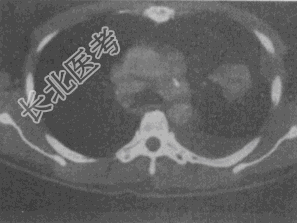

- 单项选择题患者,女, 68岁,咳嗽伴胸痛胸闷1个月, CT检查如图,最可能的诊断为

A、左上肺不张

B、左上肺周围型肺癌伴胸膜转移

C、左上肺血管瘤

D、左上肺软骨肉瘤伴胸膜转移

E、左上肺结核